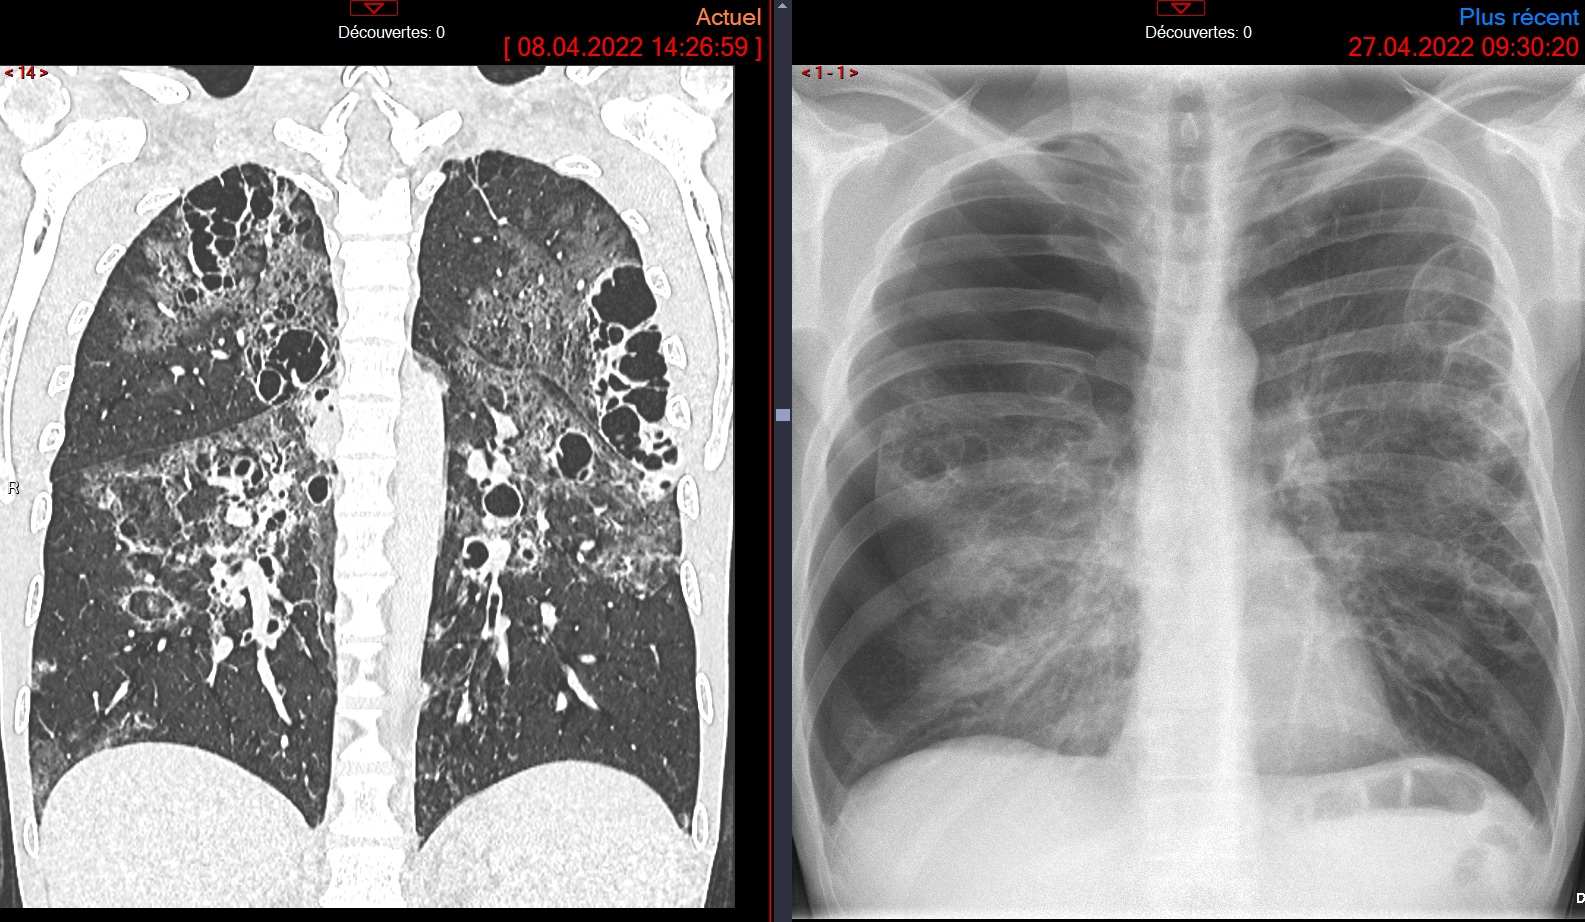

Cas

PCP kystique avec pneumothorax, SIDA

PCP kystique avec pneumothorax, SIDA

Pneumocystose pneumo jorivenci jancovici jiro joiv jroveci jiroverci jirovercii jiroveci